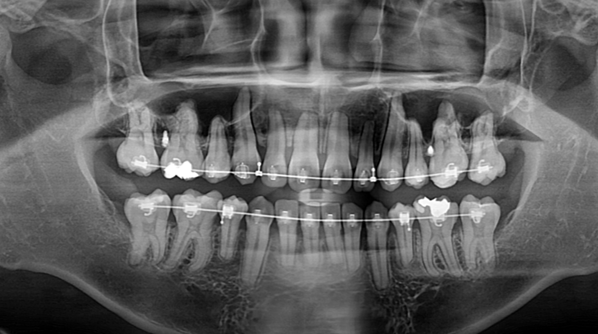

교정치료 중 필요한 사랑니 발치

Before

교정 치료와 동반하여 매복 사랑니를 발치한 케이스 입니다.

때로는 교정 치료를 위해서 사랑니 발치를 해야하는 케이스도 있습니다.